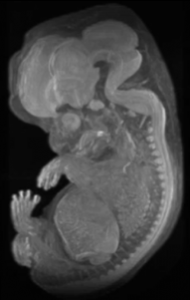

ヒト胚子期のMRI画像から再構成した立体画像です。